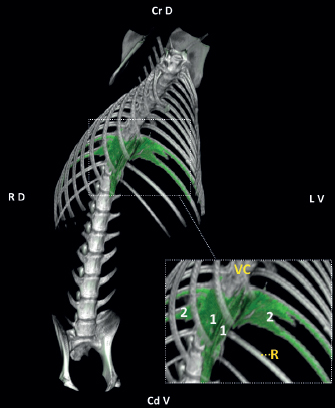

The injection site varied between T8-9 and T12-13. Contrast was identified in the paravertebral space in 92% of the injections (12/13). The right injection in dog number 7 was directly performed in the mediastinum. The distribution pattern observed in all the injections within the TPV space (12/12) was linear and intercostal (Fig. 4). The median (range) linear spread of the contrast was 7 (5–10) spinal nerves and involved 3 (2–8) intercostal spaces. Forty-two percent of the injections within the TPV space (5/12) were distributed beyond the psoas muscle origin, reaching lumbar regions. The sites of injection and the spread of the contrast-dye within the TPV space are illustrated in Figure 5.

Fig. 4. Three-dimensional volume rendering of the CT imaging study showing the linear (1) and intercostal (2) distribution of the contrast (green appearance) for the dog number 8 (injection site T12–T13). (R): 12th rib; (VC): vertebral column. See orientation landmarks as follows: (Cd V): caudo-ventral; (Cr D): cranio-dorsal; (LV): left-ventral; (RD): right-dorsal.